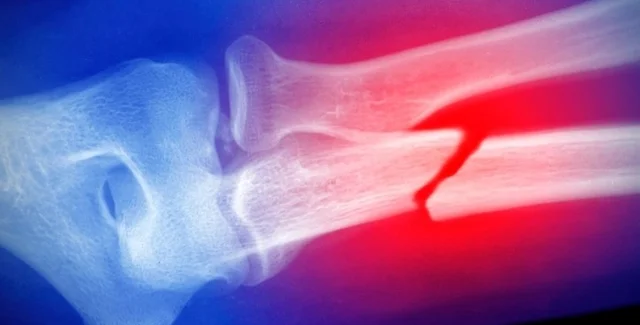

Множинні переломи в дитинстві можуть бути "небезпечним дзвіночком" | Фото: Getty Images